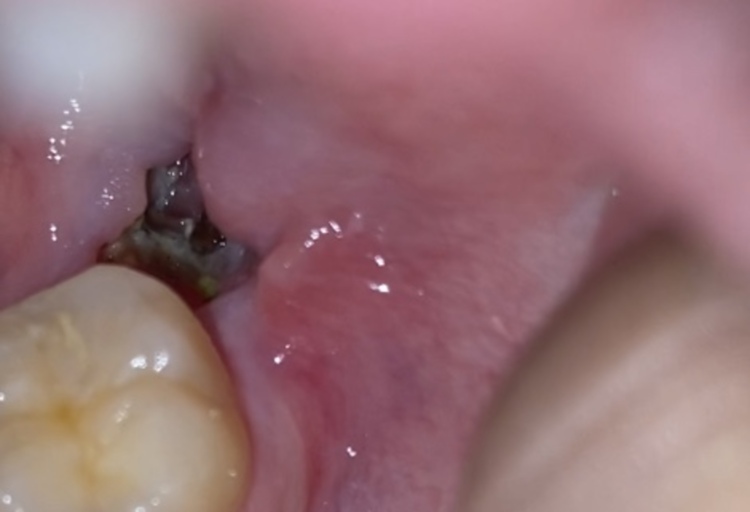

This Hole Left From My Wisdom Tooth Where You Can See The Bone R Popping

What Is This Grey Stuff In My Wisdom Tooth Extraction Site